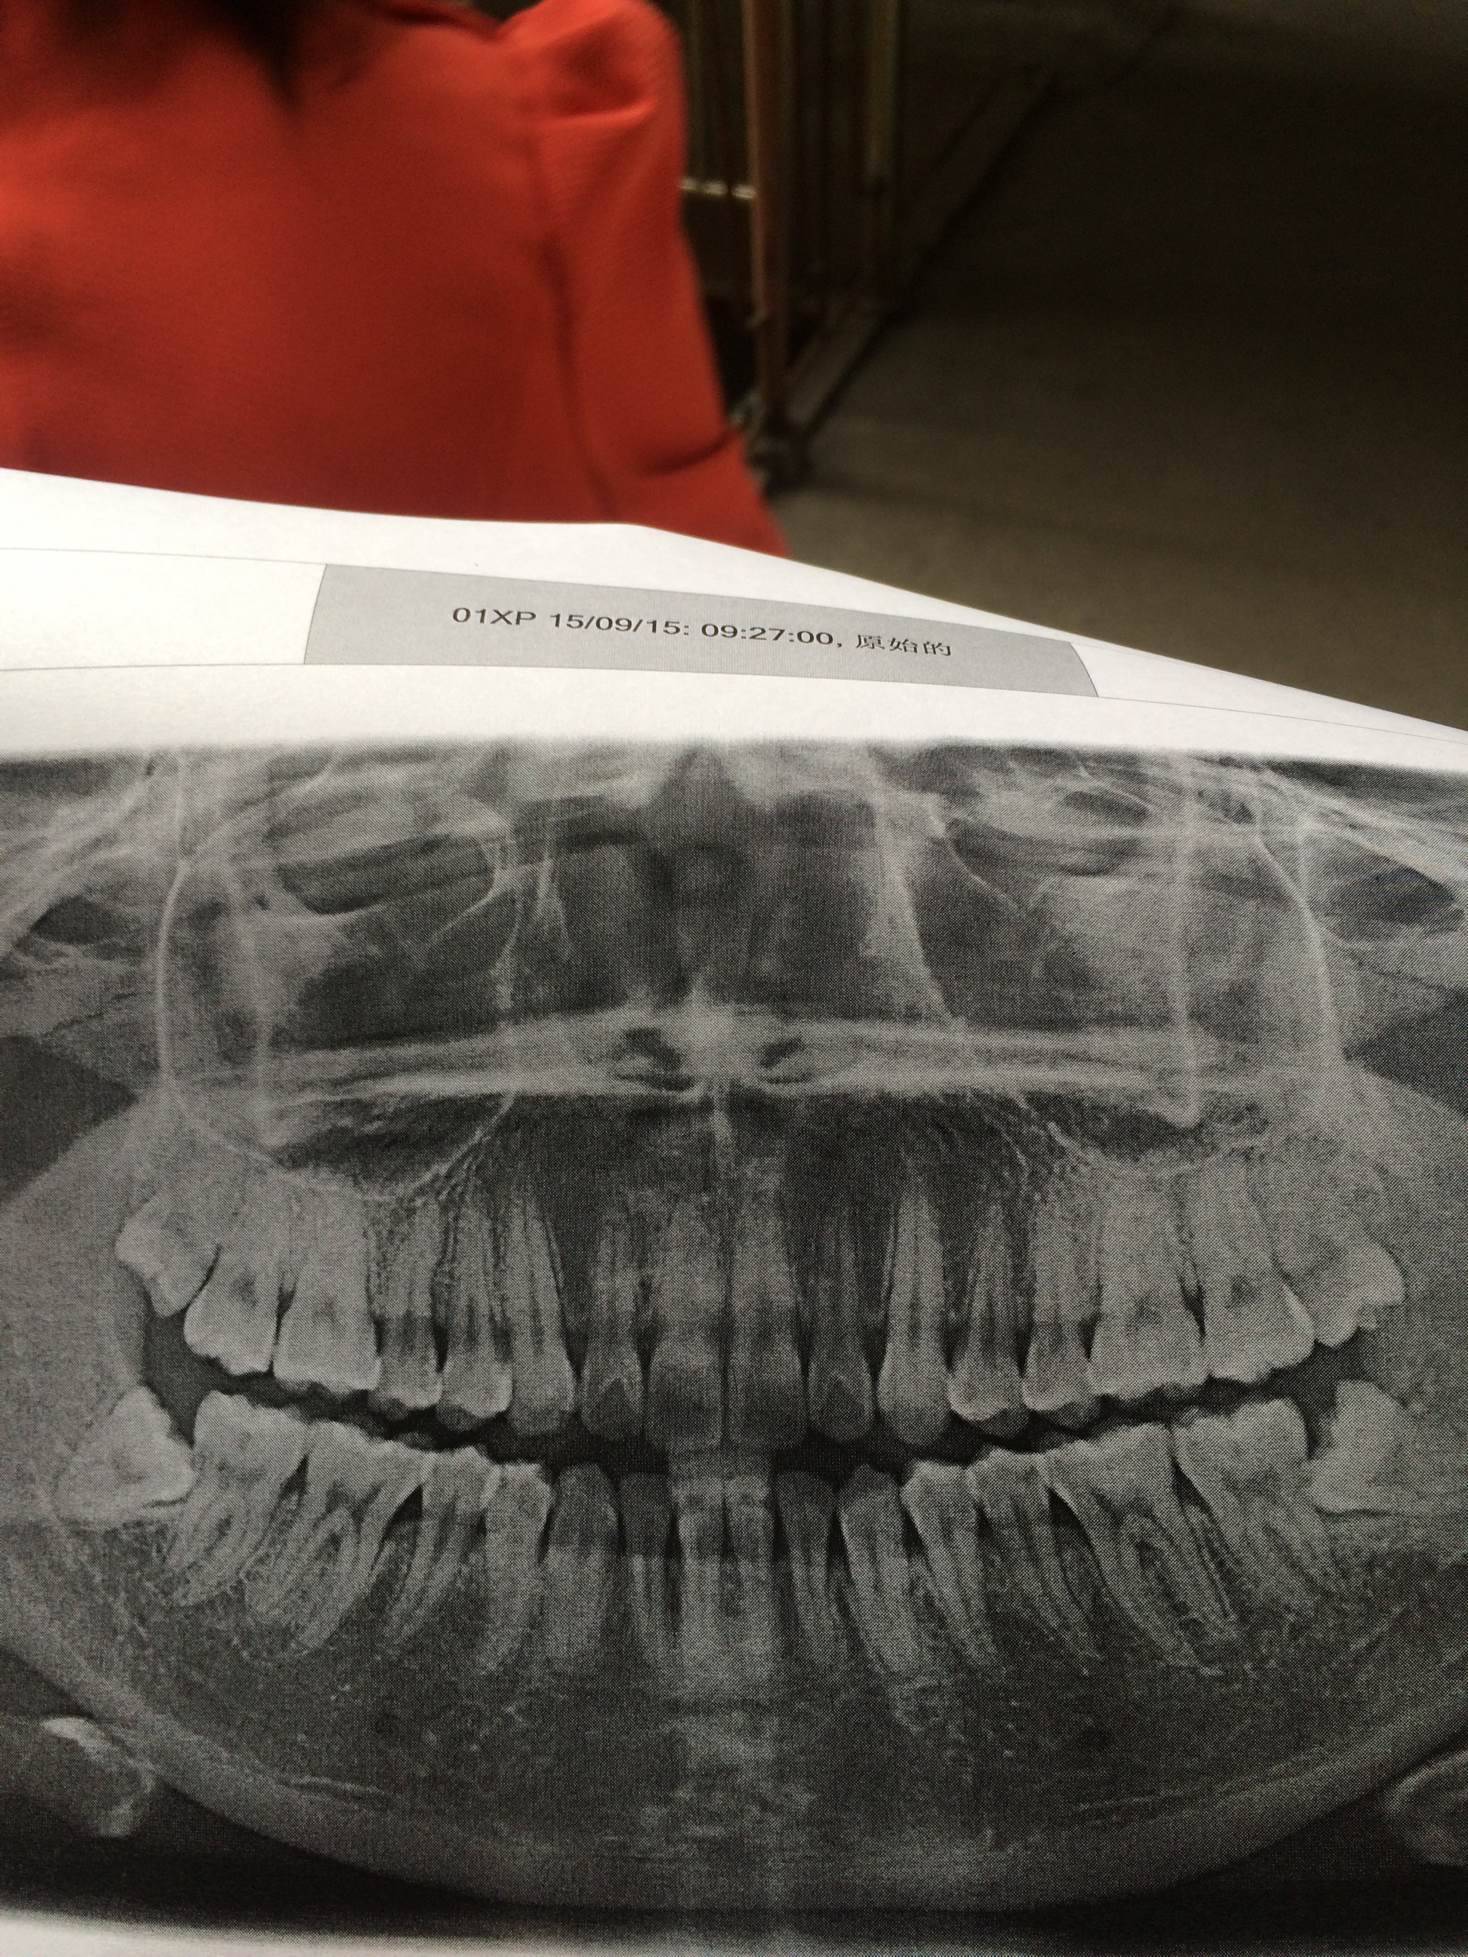

那两颗智齿怎么长成这样

我拔了两颗智齿,还剩两颗也是歪着长的,没用的牙长它干吗,哎。

是挺可恶的,我上下左右4颗全拔了,前3个是没得病前拔的。最后一个是今年初拔的,吃消炎药都消不下。最后还是住院输了几天液。太惊险了!最怕进牙科。